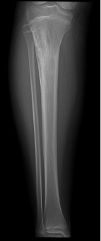

ADAMANTİNOMA

Düşük dereceli, ender rastlanan habis bir kemik tümörüdür. Adını benzer bir dokudan çıkan bir çene tümöründen alır. Uzun kemiklerdeki lezyonlar çenedekinden farklı olarak metastaz yapabilirler. Her iki cinste özellikle de 20-50 yaş arasında sık görülür. Lezyonların %90'ı tibiadadır. Humerus, ulna, femur ve diğer kemiklerde de görülebilir. Hastalar hekime yıllardır devam eden hafif bir ağrı ve yavaş yavaş belirgin hale gelen sert bir şişlik şikayeti ile başvurular. Bazen patolojik kırık olabilir.

Adamantinoma bazen fibröz displazi ile birlikte olabilir, ya da bunu taklit edebilir. Biyopsi ile tanı konulduktan sonra kemoterapi ve radyoterapi duyarlılığı olmadığı için tedavi seçeneği olarak geniş sınırlar ile cerrahi rezeksiyon uygulanır.